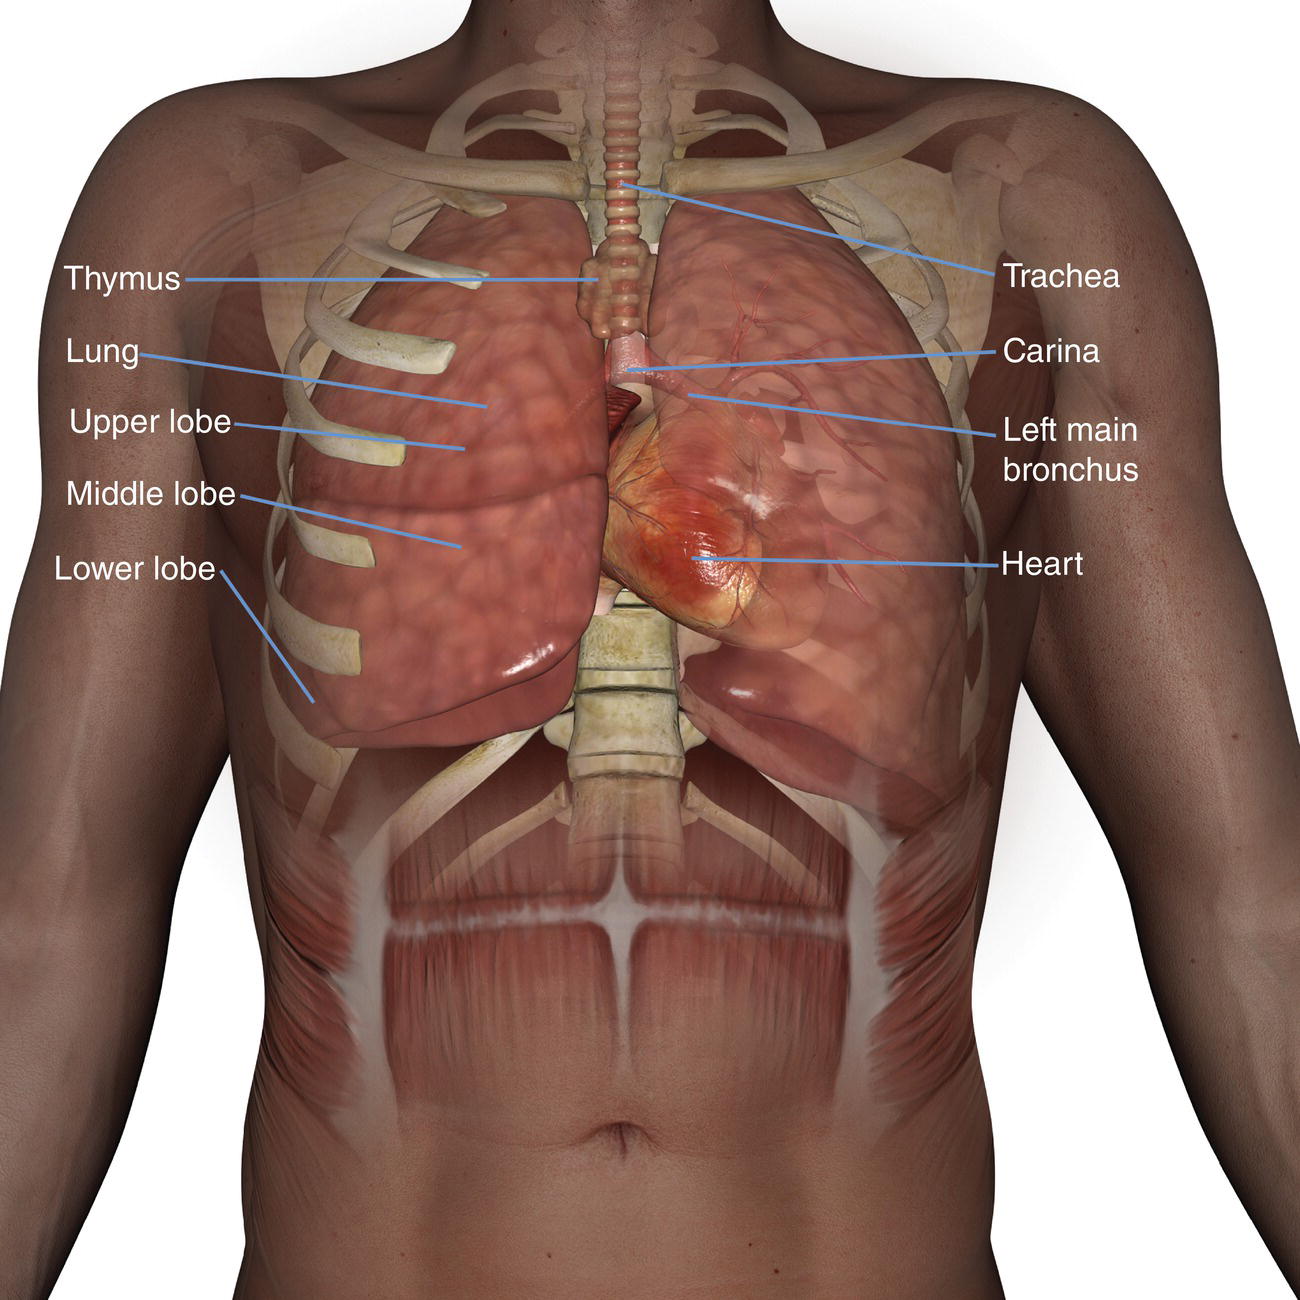

Анатомия Сердца: Расположение и Функции